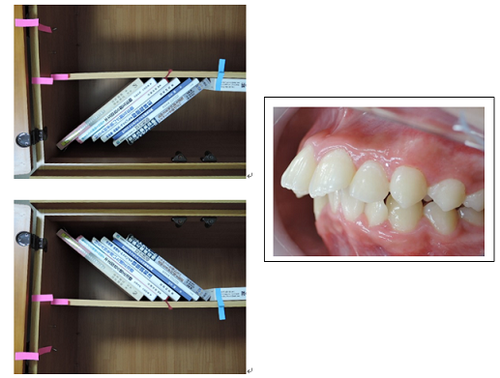

MEAW(マルチループ)を利用して歯を動かす隙間の作り方は2種類あります。

②ふたつ目は以下の様な原理です。

①では歯が近心側に綺麗に傾いた場合ですが、歯が内側(舌側)に傾く事もあります。

この場合もMEAW(マルチループ)によって内側(舌側)に傾むいた歯を起こしていきます。

MEAW(マルチループ)を利用して歯を動かす隙間の作り方は2種類あります。

①ひとつ目は以下の様な原理です。

これを身近な7冊の本を使って説明していきましょう。